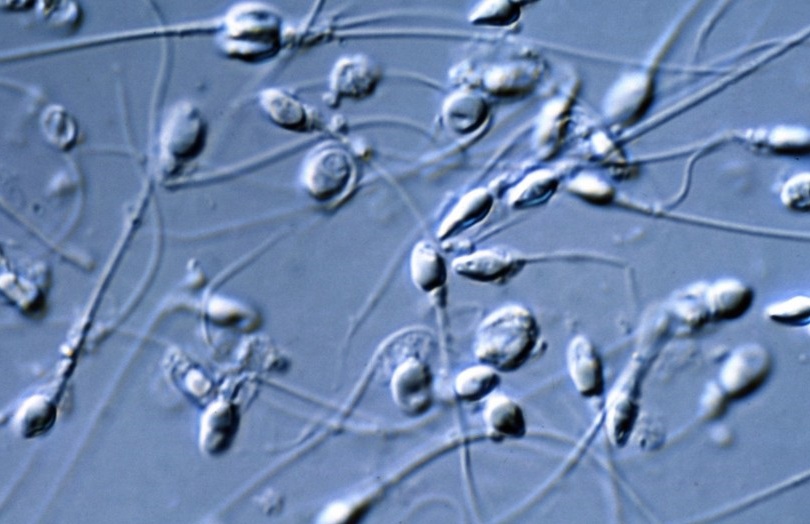

ПовечеСпермален анализ - номенклатурни термини

Публикувано на: 01.10.2010 Термините в тази статия описват спермалните показатели и са съобразени с петото издание на СЗО за...

ПовечеСпермален анализ - референтни граници

Публикувано на: 01.10.2010 Референтните граници в тази статия са съобразени с петото издание на СЗО за оценка на еякулата при м...

ПовечеСпермограма, спермограма, спермограма

Публикувано на: 27.05.2007 "Вчера последният за деня пациент ми каза “Докторе, никога дори и не съм си представял, че ще стигна...

ПовечеСпермата - автор Nikam

Публикувано на: 09.01.2007 Спермата е най-загадъчната и свързана с митове течност от човешкото тяло. Още от най-древни времена,...